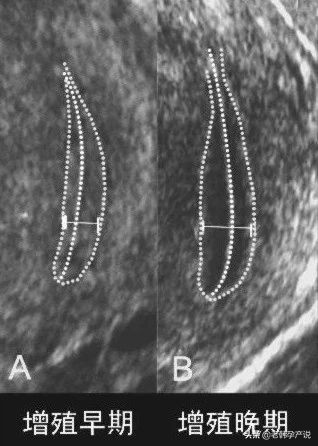

2.增殖期

月经周期的5-14天。这是内膜从“0”开始逐渐生长的过程,所以这个时期也是内膜最薄的时期,大约在0.5-1.0cm,超声检查可见明显的三线征

上图是优势卵泡直径达到18mm时子宫内膜的图像,呈明显三线征,中间的宫腔线回声强,上面的一条线以及下面一条线与宫腔线之间的组织呈低回声。